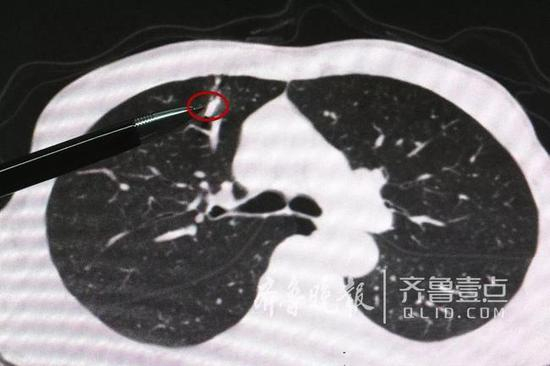

拍完片,做完CT检查以后,接诊的烟台山医院心胸 外科主任医师杨军发现:患者右肺上叶有一个长约1.5厘 米的异物,胸腔内出现了积血、积气。他结合患者的工 作情况断定患者是被锻压产生的金属碎片击伤。

“子弹”距肺上叶血管仅1毫米

“2000吨级锻压机锻压时产生的金属碎片,速度快 、威力大,好比是从枪膛里射出的子弹!”姜文升副主 任医师称,这颗“子弹”穿透了患者的胸部,裂伤肺部 ,并留在了肺内。“最险的是,这枚‘子弹’离肺上叶 血管只有1毫米的距离。如果‘子弹’移位割伤血管,可 以造成患者肺内出血;假如‘子弹’体积相对较小,它 还可能进入血管,随着血液循环而在体内游走,造成不 可预计的损伤,甚至危及生命!”姜文升副主任医师告 诉记者,如果异物击中的位置再偏一点儿,患者的肺组 织再薄一些,它可能伤及主动脉,这样就需要进行开胸 手术;如果异物击穿的是左肺,那么伤及心脏的可能性 会大一些,“所以说,患者的遭遇看似并不复杂,实则 有着诸多的不确定性,可谓危机重重!”